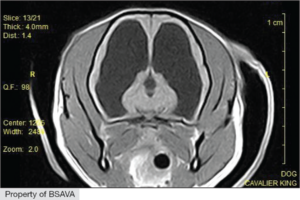

Serum cardiac troponin I levels were elevated in dogs with acute ischaemic stroke, although they had no prognostic value in this preliminary study. Cerebrovascular disease is a common cause of acute neurological dysfunction in dogs but no prognostic biomarkers have yet been identified. Cardiac troponins are routinely used as biomarkers for the diagnosis of acute myocardial infarction in humans, and increased troponin concentrations have been detected in both congenital and acquired heart diseases of dogs.

Read more and access the publication